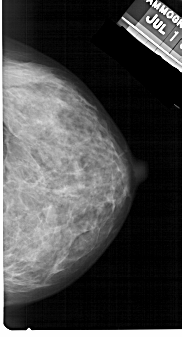

A_1392_1.LEFT_MLO

LEFT_MLO LINES 5491 PIXELS_PER_LINE 2776 BITS_PER_PIXEL 12 RESOLUTION 43.5 OVERLAY